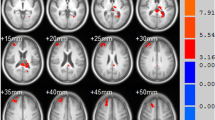

Mild cognitive impairment (MCI) is common in patients with Parkinson’s disease (PD), yet the underlying neural mechanisms of this disease state remain unclear. We investigated alterations in the spontaneous brain activity of PD patients with MCI (PD-MCI) relative to cognitively normal PD patients (PD-CN) and healthy control (HC) subjects. In this work, 13 PD-MCI patients, 16 PD-CN patients, and 16 HC subjects completed resting state functional MRI. Spontaneous brain activity was measured by calculating amplitude of low frequency fluctuation (ALFF) values across the whole brain. Between-group differences and correlations between ALFF values and cognitive test scores were analyzed. ALFF values decreased in the right superior temporal gyrus and increased in the left middle temporal gyrus and left superior frontal gyrus of PD-MCI patients compared with PD-CN patients. In the PD-MCI group, ALFF values in the left middle temporal gyrus were negatively correlated with Montreal Cognitive Assessment and vocabulary test scores, and the ALFF values in the left superior frontal gyrus were negatively correlated with vocabulary test scores. Our study demonstrates that PD-MCI is associated with abnormal spontaneous brain activity in the temporal and frontal lobes. These findings inform the underlying neural mechanism of cognitive impairment in PD.